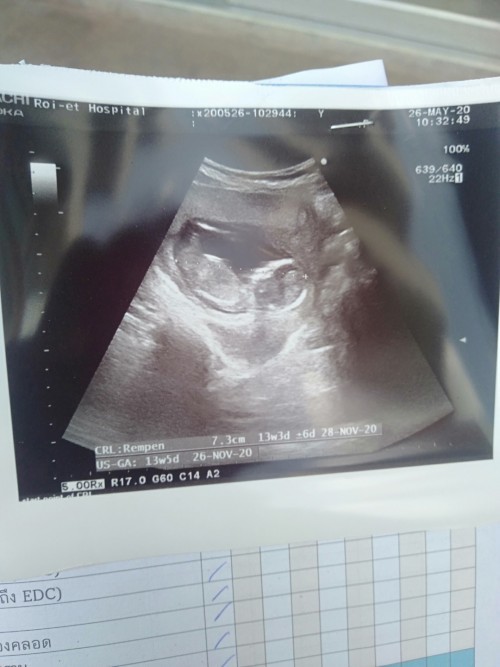

แม่ๆคนไหนมีภาพอัลตร้าซาวด์ประมาณ13วีคบ้างคะ ของเรา13วีค ภาพแบบนี้ค่ะ ดูไม่ออกเลย?

13วีค6วันค่ะแม่